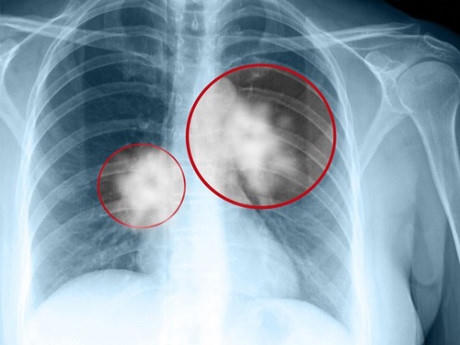

Vậy, căn bệnh ung thư phổi nguy hiểm và có sức tàn phá như thế nào đối với cơ thể con người. Theo các chuyên gia về ung thư, ung thư phổi là một trong số những căn bệnh có tỷ lệ mắc nhiều nhất hiện nay đặc biệt là ở nam giới, độ tuổi mắc bệnh ung thư phổi nhiều nhất là từ 45-70 tuổi, tuy nhiên xu thế hiện nay đang ngày càng trẻ hóa.

Điều đáng nói, căn bệnh ung thư này có tỷ lệ người mắc tử vong ngay trong năm đầu tiên phát hiện bệnh có tỷ lệ rất cao chiếm khoảng 70%, thậm chí có trường hợp từ khi mắc bệnh và tử vong chỉ trong vòng chưa đầy 6 tháng.

BS Phương cho rằng, ung thư phổi được chia làm hai loại, ung thư phổi không tế bào nhỏ và ung thư phổi tế bào nhỏ. Đối với ung thư phổi tế bào nhỏ, bệnh tiến triển rất nhanh, di căn sớm, tái phát nhanh, nhạy cảm với hóa chất.

“Có thể hình dung rằng, ung thư phổi tế bào nhỏ rất khó khăn trong việc điều trị, có thể nói nôm na là khi chặt được đầu nọ thì đầu kia nó đã phát triển rồi”, BS Phương chia sẻ.

Còn đối với ung thư phổi không tế bào nhỏ, bệnh tiến triển chậm hơn, đáp ứng được với hóa chất, loại ung thư này chiếm tỷ lệ khoảng 85 đến 87% tổng số ca.